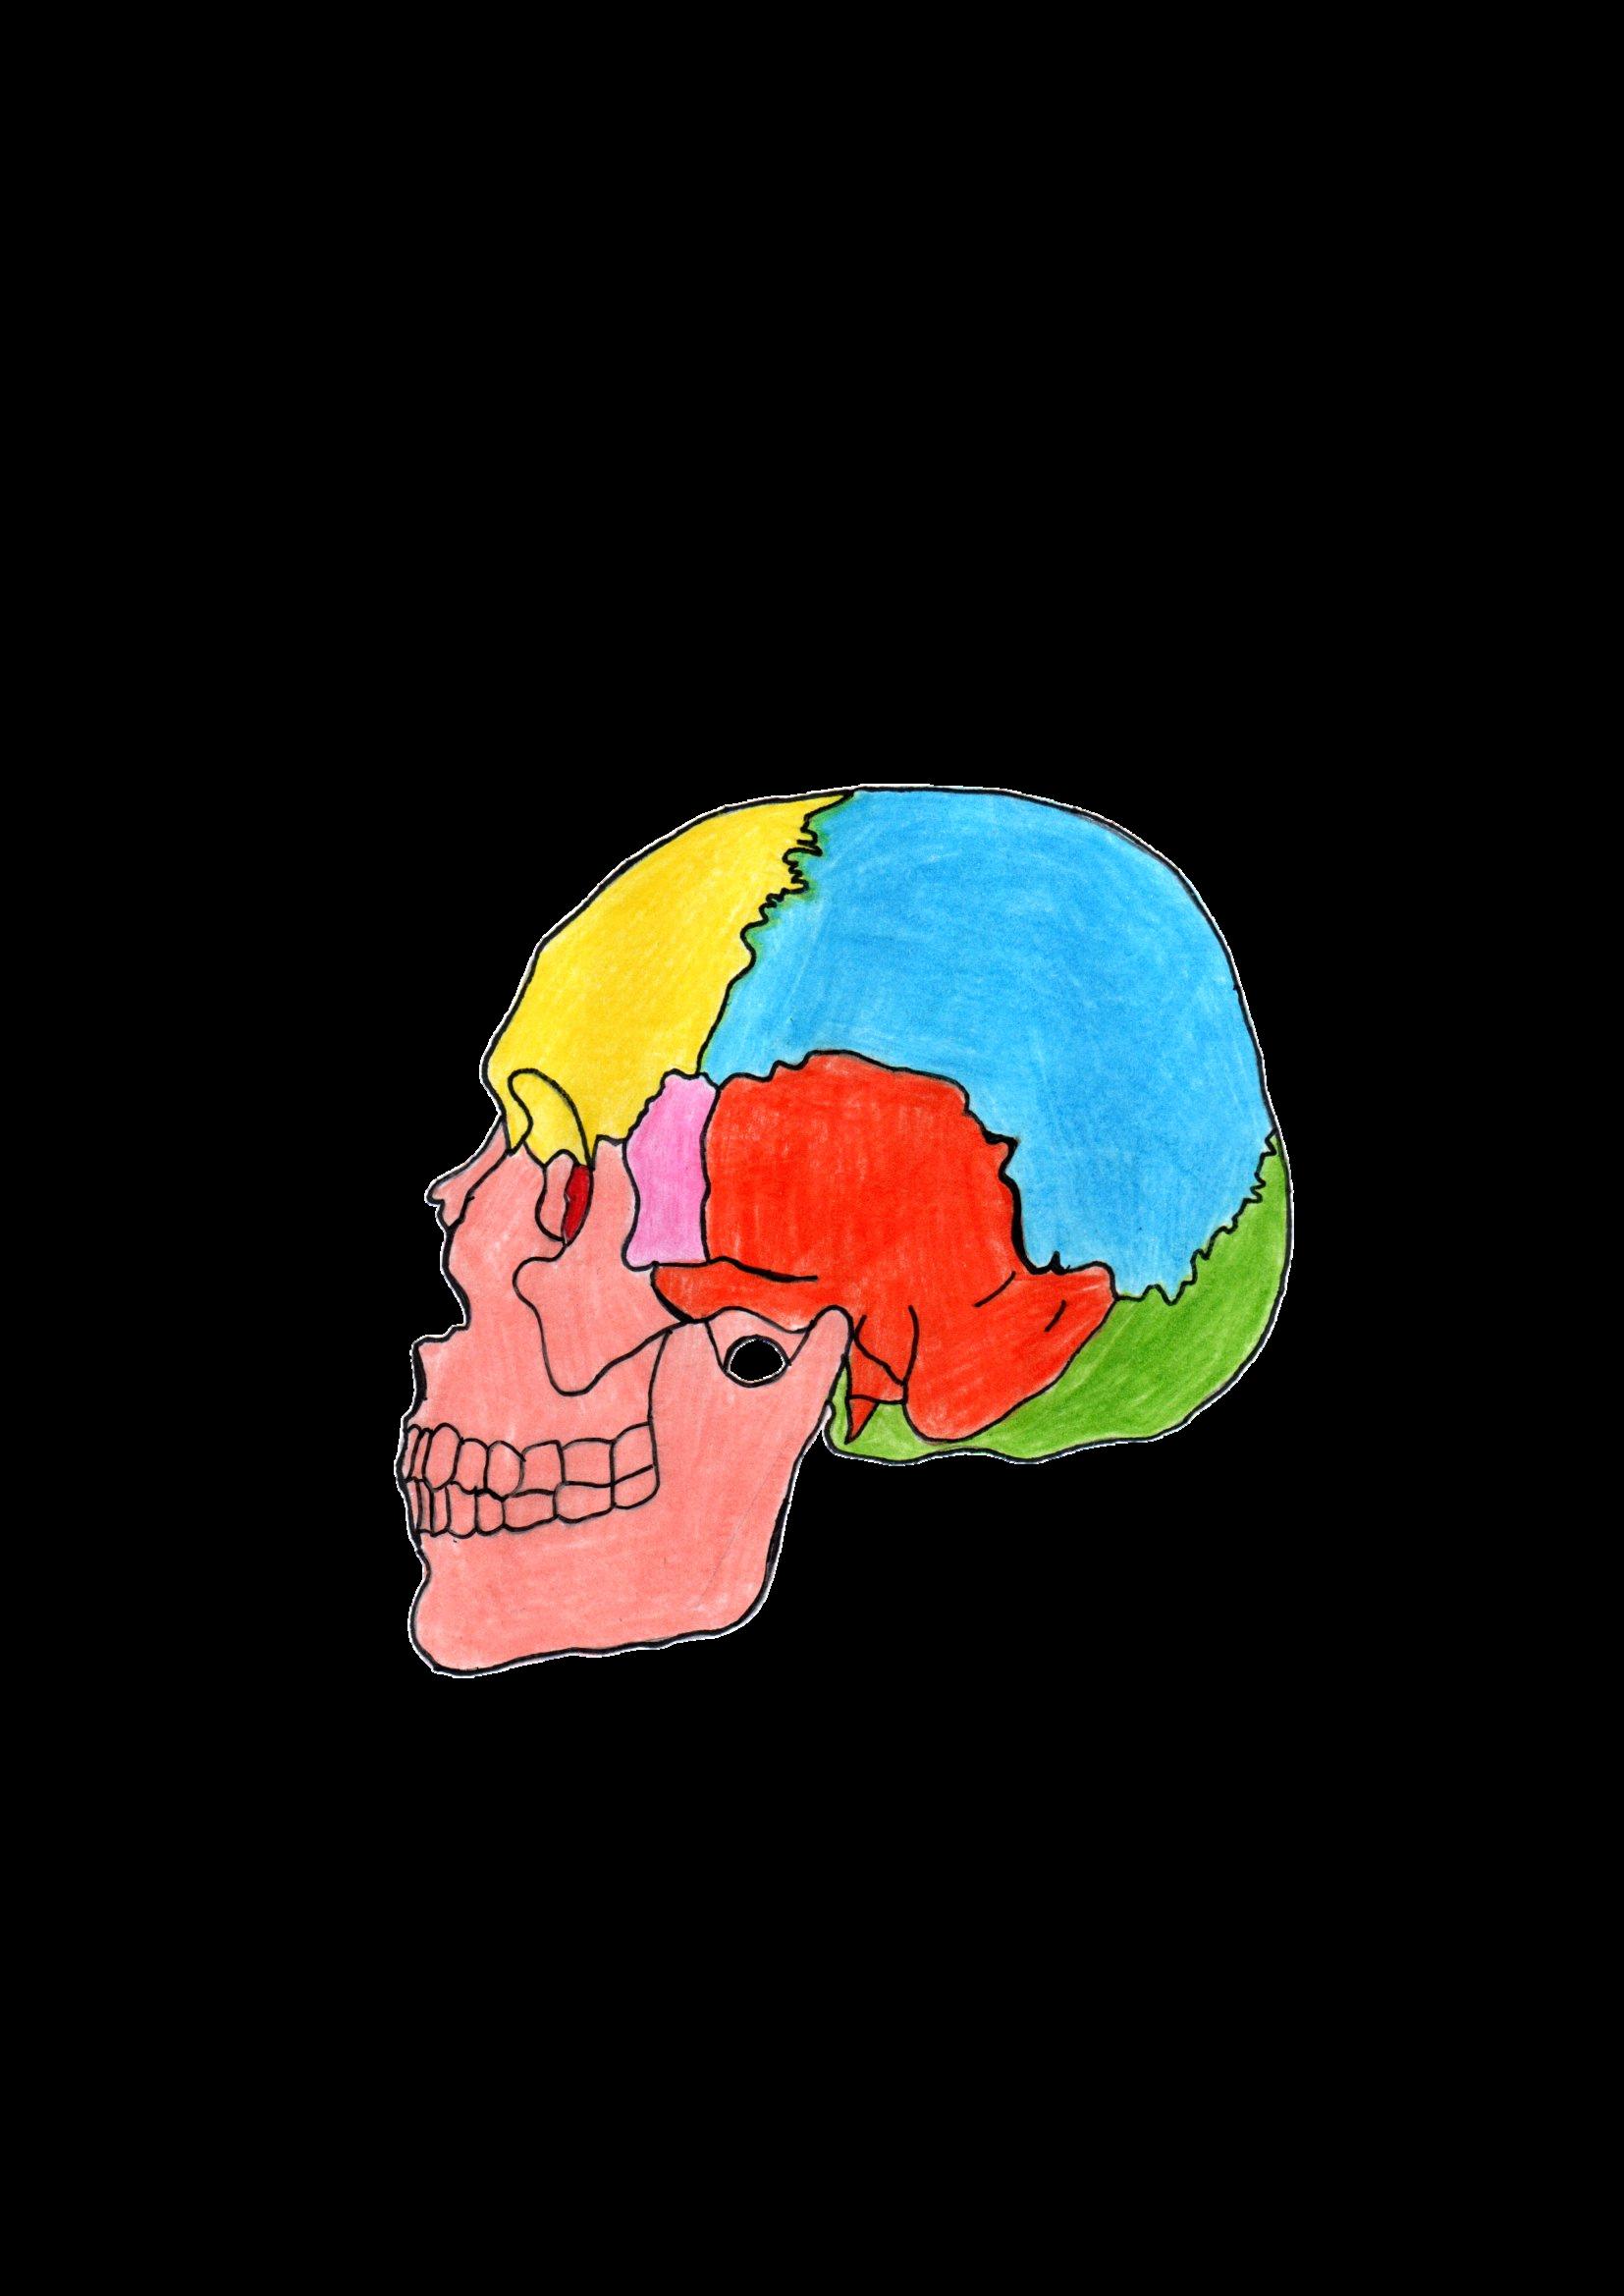

ESFENOIDES

EL CRÁNEO

PARIETAL TEMPORAL

ETMOIDES

FRONTAL OCCIPITAL

NASAL LACRIMAL

MAXILAR

CORTENE NASAL INFERIOR VÓMER

MANDIBULA

El cráneo, esta situado en la cabeza junto con el macizo óseo Ya que es una estructura resistente, es la encargada de proteger al cerebro y todas las partes del sistema nervioso central También sirve como un escudo protector ante goles muy fuertes y que no se dañen otras partes.

PALATINO

CIGOMÁTICO